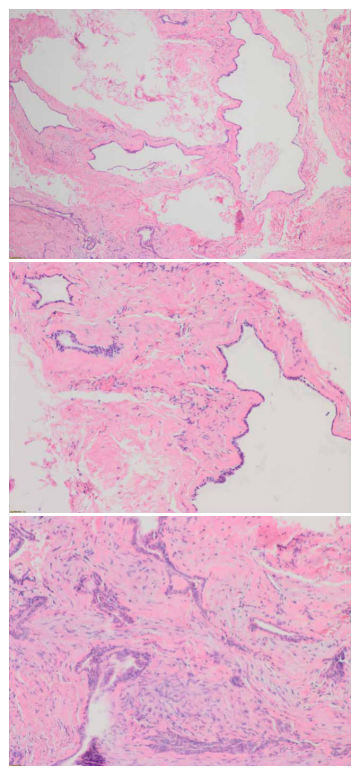

El diagnóstico de confirmación tuvo como resultado un mucocele de retención. Los fragmentos analizados estaban constituidos por tejido conectivo densamente colagenizado en el que se observa la presencia de lesiones quísticas con un epitelio cuboidal y aspecto salival. No se observaron fenómenos inflamatorios (Figura 7).

fenómenos inflamatorios y el tejido conectivo sugiere una densa

colagenización.